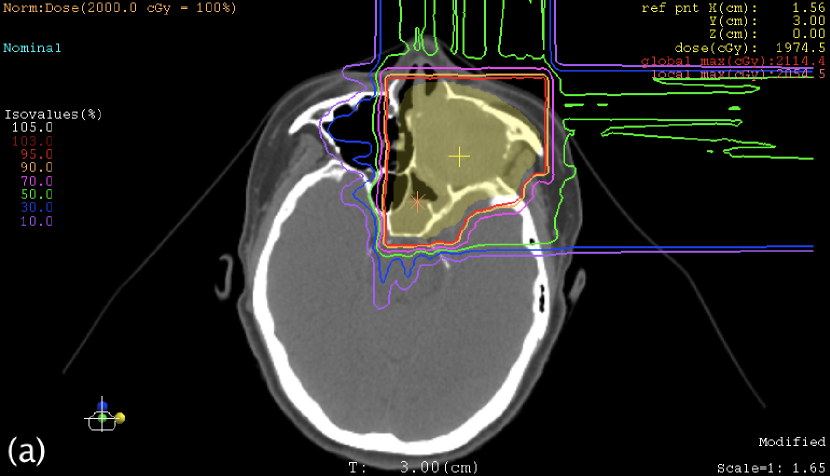

III.3 Case study

Table 3 shows the maximum WE thicknesses of the range compensators. Except for the posterior beam in the sacrum case, range compensation was large as it had been expected for oblique-incident beams. Figures 4 and 5 show the plan dose distributions, in which the reduction of clinical dose was 0.30% at the isocenter in the sacrum case, 0.75% at the isocenter in the nose-and-sinus case, and mostly within 1% in these targets. In the nose-and-sinus case, the dose reduction greater than 2% occurred only in the air that happened to be included in the dose-calculation volume. Relatively speaking, the dose reduction was greater in the posterior part of the sacrum target and in the anterior-left (away from nose) part of the nose-and-sinus target, which was caused by locally shallower target depth and hence larger range compensation in the fields.